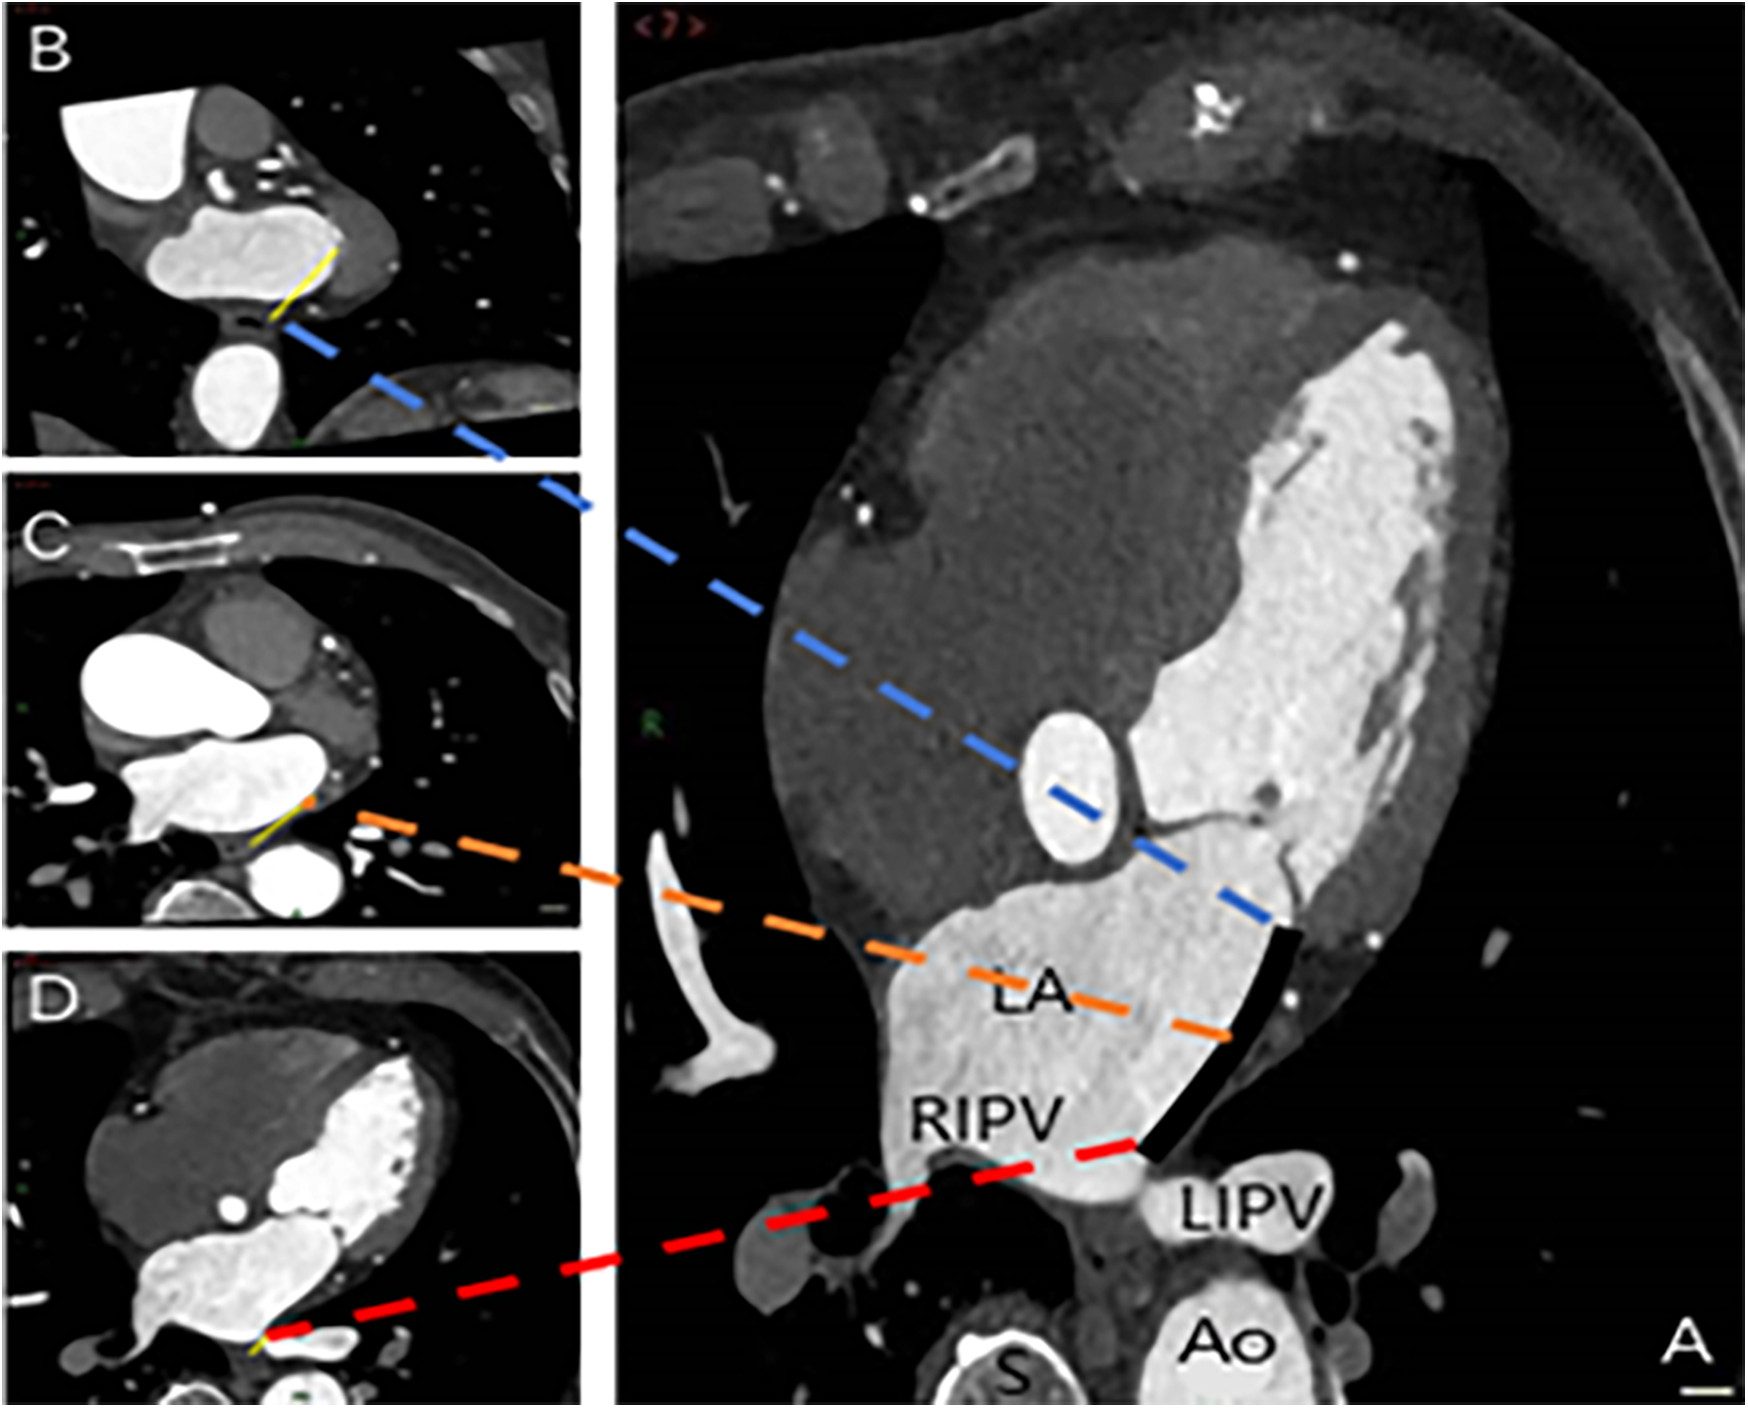

The spatial measurements of the MI were meticulously captured using the post-processing techniques of multiplanar reformation and volume rendering facilitated by CT, aiming to assess its proximity to the surrounding esophagus. The measurements were systematically recorded at three strategic locations: the intersection of the upper end of the MI and the LIPV (Level 1), the midpoint of the MI (Level 2), and the level of the mitral annulus (Level 3) (Figure 3). Cross-sectional and sagittal images, as illustrated in Figure 4, were utilized to accurately determine the proximity of the MI to the esophagus at these levels, providing a detailed assessment of their spatial relationship.

Figure 3

Spatial measurements of MI and its proximity to the esophagus. The measurements were taken at three key locations: Level 1 (intersection of the upper end of MI and LIPV) in image D, Level 2 (midpoint of MI) in image C, and Level 3 (level of the mitral annulus) in image B. The annotations are as follows: Ao, aorta; LA, left atrium; LIPV, left inferior pulmonary vein; RIPV, right inferior pulmonary vein; S, spine; black solid line, MI distance measurement; yellow solid line, distance from the three levels to the esophagus.